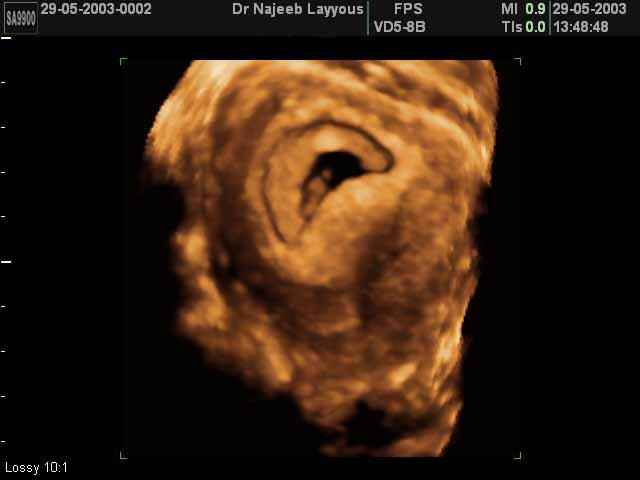

- 3D Photos Ecographie du Premier Trimestre

3D Photos Ecographie du Premier Trimestre (Photos d’échographie de tôt grossesse)| Dr N Layyous